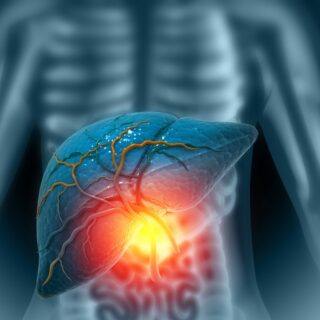

Die Leber entgiftet

Das Organ nimmt Eiweiß auf, speichert Kohlenhydrate und bildet mit der Gallenblase ein effektives Duo. Aber damit nicht genug: Die rotbraune Drüse wandelt Schadstoffe wie Alkohol in unschädliche Stoffe um und baut diese in der Folge ab. Natürlich funktioniert dies nur bis zu einem gewissen Grad. Bei einer erhöhten Schadstoffaufnahme gerät die Leberfunktion aus dem Gleichgewicht.

Neben dem Zellgift Alkohol leidet das Entgiftungsorgan unter dem Konsum von Nikotin. Demnach schadet Rauchen nicht nur der Lunge, sondern auch der Leber. Da die Leber sich mit den meisten Stoffen, die wir essen und trinken, direkt auseinandersetzen muss, gelten ein übermäßiger Zuckerkonsum, ungesunde Fette und Medikamente als weitere Gefahrenquellen. Die Fettleber ist in den vergangenen Jahrzehnten zu einer echten Zivilisationskrankheit geworden. Die Fetteinlagerung ist in vielen Fällen ein Resultat aus einem übermäßigen Alkoholkonsum, einer ungesunden Ernährung und Bewegungsmangel. Da Erkrankungen vor allem im Anfangsstadium oft ohne Symptome auftreten, sind geeignete Präventionsmaßnahmen umso wichtiger. Mit einer Bestimmung der Leberwerte können viele Erkrankungen bereits im Frühstadium identifiziert werden. Darüber hinaus heben Experten immer wieder Vorzüge von körperlicher Aktivität hervor. Wir können das Organ durch regelmäßiges Sporttreiben entlasten und zugleich Übergewicht entgegenwirken. Eine Win-Win-Situation!